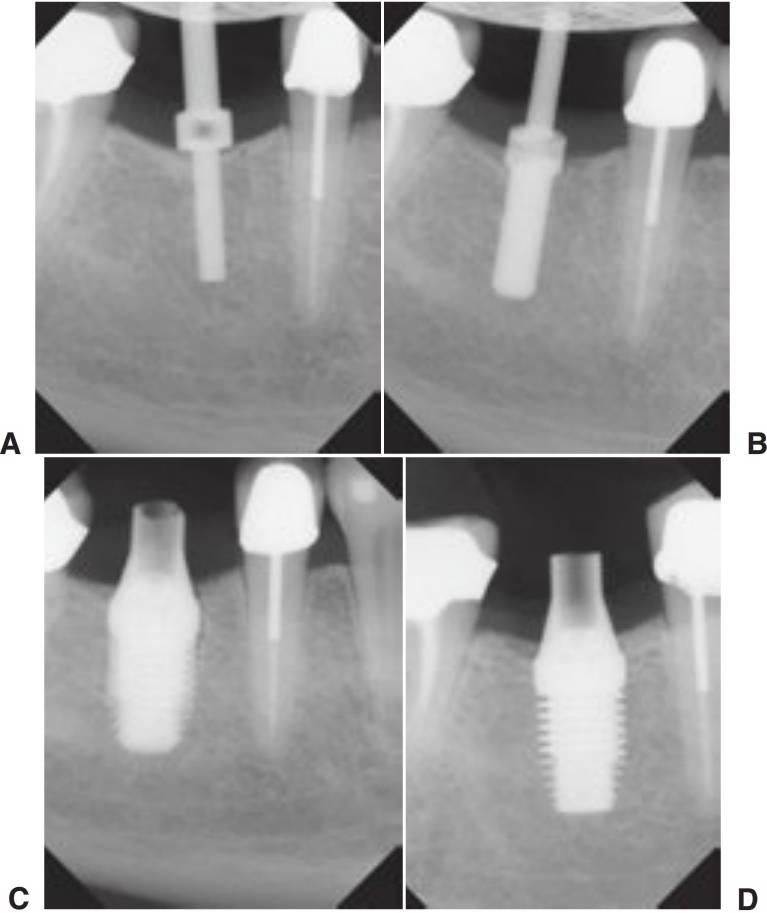

Imágenes intraoperatorias

El empleo de imágenes quirúrgicas ha cambiado dramáticamente la manera en que se completa la cirugía implantológica (cuadros 3-13 y 3-14). En el pasado las desventajas de las radiografías periapicales perioperatorias han condicionado un tiempo de inefíciencia. Para verificar el posicionamiento y localización de un sitio de osteotomía o para la identificación de una estructura vital, el procesamiento de una película de radiografía estándar puede llevar hasta 6 minutos. A causa de ello, los practicantes verificaban raramente el posicionamiento de las estructuras anatómicas durante la cirugía. Con la nueva tecnología radiográfica digital se consiguen imágenes instantáneas, permitiendo completar múltiples imágenes en una fracción de tiempo. Las ventajas adicionales de las imágenes digitales intraoperatorias incluyen la manipulación de las imágenes, su calibración, mediciones exactas y el posicionamiento, y el mantenimiento de un protocolo aséptico (figs. 3-22 y 3-23).

Imágenes del pilar dental y del componente protésico

En el momento de hacer una evaluación para la transferencia de impresiones junto con la colocación del componente del pilar de dos piezas, se deberían tomar radiografías para verificar que la adaptación sea segura. Se deberían emplear radiografías intraorales debido a su alta resolución geométrica para evaluar cualquier discrepancia de ajuste.

En cualquier caso, se debe de tomar la precaución de que el haz de rayos X sea dirigido hacia un ángulo correcto del eje longitudinal del implante. Incluso una leve angulación permitiría que no se detectara un pequeño espacio. Cuando el posicionamiento para las radiografías periapicales es difícil, se pueden emplear radiografías de aletas de mordida o panorámicas (figs. 3-25 y 3-26).

Es necesario hacer una radiografía posprotésica para utilizarla como imagen básica para futuras evaluaciones del ajuste del componente y también para la evaluación del nivel de hueso marginal. Se deben tomar precauciones para asegurar que se ha llevado a cabo el ajuste adecuado de todos los componentes. Adicionalmente, debe determinarse el nivel de hueso marginal para futuras evaluaciones.